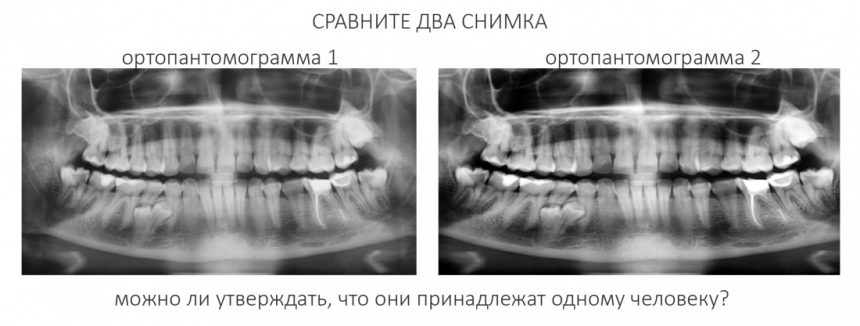

По мнению абсолютного большинства, под периимплантитом подразумевается воспалительный процесс, сопровождающийся выраженными органическими (видимыми) изменениями окружающих имплантат тканей. Чаще всего мы говорим про периимплантит, когда видим резорбцию костной ткани вокруг имплантата:

С этого момента возникает довольно серьёзная методологическая проблема: далеко не всегда деструкция костной ткани сопровождается хоть какой-то воспалительной симптоматикой. Как, например, здесь:

Снимок сделан примерно через 8 лет после имплантации. 65-летняя пациентка никакой воспалительной симптоматики не отмечает, говорит, что никогда ничего не болело и не воспалялось. Можно ли считать такой случай периимплантитом?

С одной стороны, убыль костной ткани налицо, но её причиной может быть, в том числе, обычная атрофия (всё же, возраст и состояние организма…). С другой, отсутствие каких-либо признаков воспалительного процесса в анемнезе и при объективном осмотре. Назвать этот случай периимплантитом нельзя, убыль костной ткани в этом случае вызван физиологической атрофией, связанной, в т. ч., с вышеозначенными причинами.

Другой момент, вызывающий бурную дискуссию: С какого момента убыль костной ткани можно считать периимплантитом?